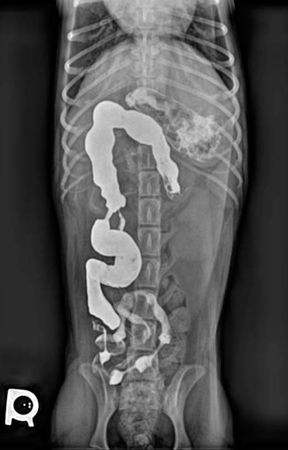

Add a little contrast to help you find your diagnosis.

Can you determine why Tupper can't handle his supper?